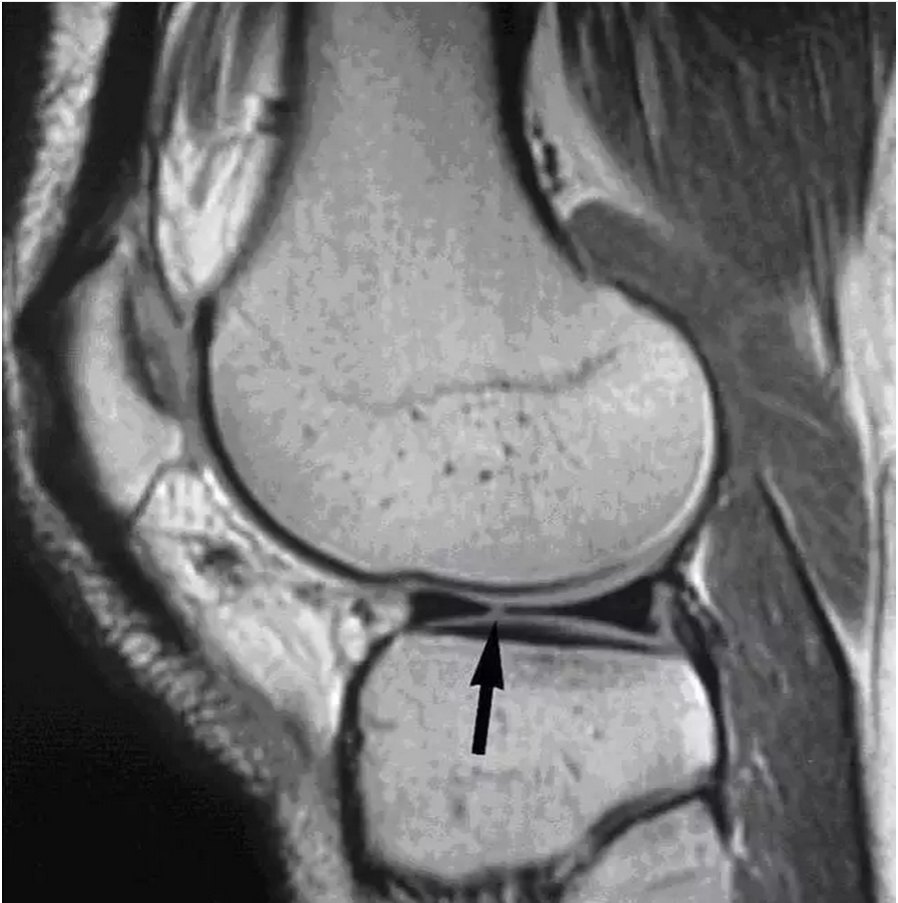

图 11 内侧半月板桶柄状撕裂——双后交叉韧带征(点击查看相关文章).